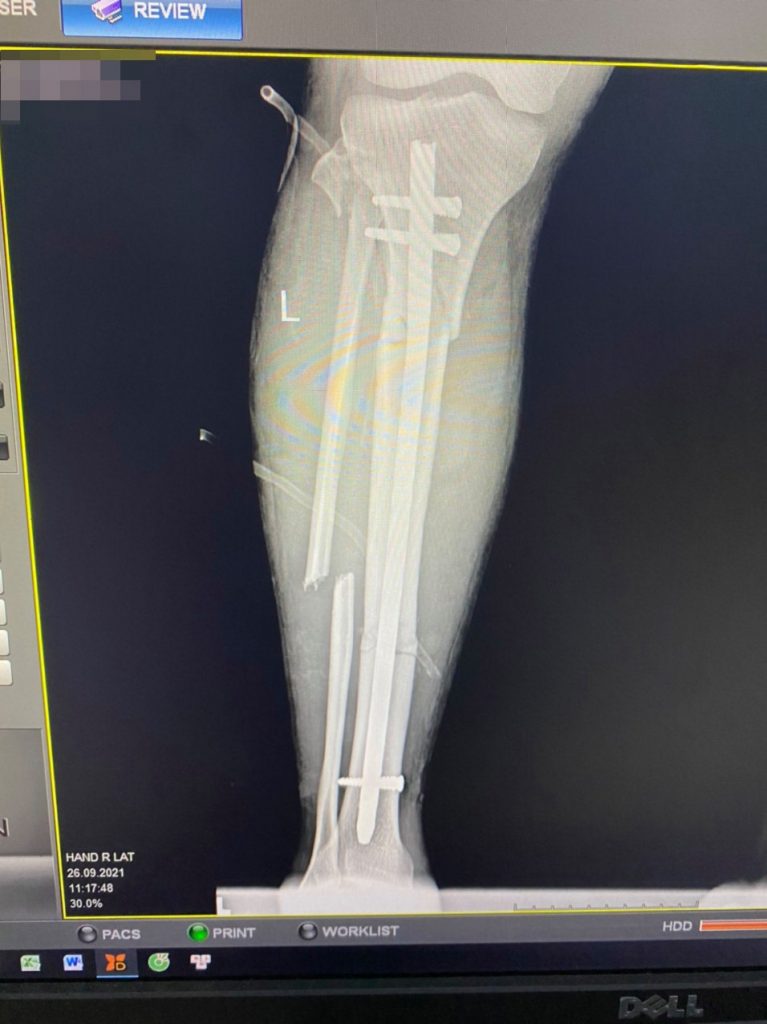

Bệnh nhân Đ. cho biết “Sau khi mổ được các bác sỹ, điều dưỡng thay băng, hướng dẫn tôi tập rất chu đáo. Tôi thấy vết thương nhanh liền, thời gian hồi phục nhanh hơn tôi nghĩ. Rất cảm ơn các bác sĩ đã mổ bằng phương pháp hiện đại cho tôi”.

Theo Bác sĩ CK2 Nguyễn Quang Chung: Trước đây những trường hợp gãy như thế này thường phẫu thuật kết hợp xương bằng nẹp vis. Nhờ phương pháp phẫu thuật kết hợp xương bằng đinh Sign ít xâm lấn, rất hiệu quả, giúp bệnh nhân có thể vận động và phục hồi sớm.